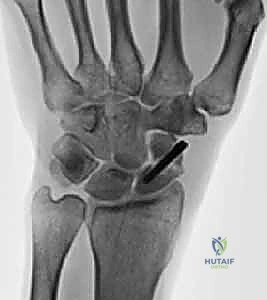

يُعرف الأستاذ الدكتور محمد هطيف بأمانته الطبية ودقته المتناهية في التشخيص. لا يعتمد فقط على الفحص السريري، بل يطبق بروتوكولاً تشخيصياً شاملاً يشمل:

- الفحص السريري الدقيق: تقييم مدى الحركة، قوة القبضة، وتحديد نقاط الألم بدقة.

- الأشعة السينية الرقمية (Digital X-rays): بأوضاع متعددة (AP, Lateral, Scaphoid view) لتقييم زوايا العظام ودرجة الانهيار.

- الأشعة المقطعية (CT Scan): وهي المعيار الذهبي لتقييم حجم العظم المتآكل بدقة ثلاثية الأبعاد، وتحديد مدى الخشونة في المفاصل المحيطة.

- الرنين المغناطيسي (MRI): لتقييم حيوية العظم (هل العظم ميت أم حي؟) وفحص الأربطة المحيطة.